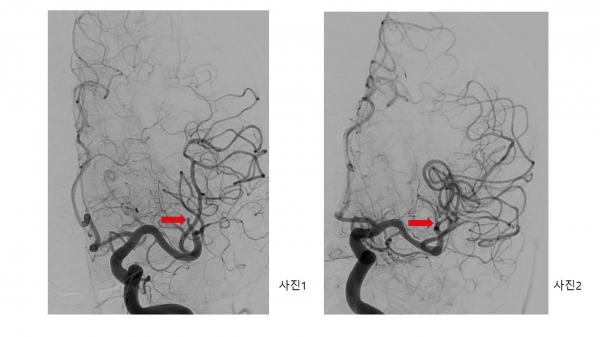

이번 시술을 집도한 신경외과 변형수 교수는 “응급 뇌혈관 조영술을 통해 환자 상태를 살펴본 결과, 왼쪽 뇌의 50%에 혈액을 공급하는 중요한 혈관이 막힌 것을 확인하고 흡입 혈전제거술을 통해 1시간 이내에 재개통술을 성공적으로 마쳤다”고 밝혔다.

뇌혈관 재개통술은 갑자기 뇌혈관이 막혀 발생한 뇌경색 환자가 골든 타임 이내에 내원했을 때 막힌 혈관을 뚫어주는 치료로 뇌 손상을 최소화할 수 있는 최선의 치료법이다.